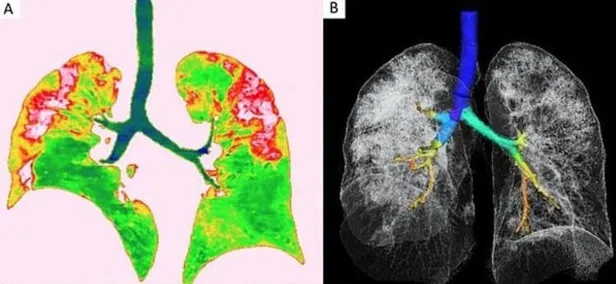

Röntgen görüntüleri ve bilgisayarlı tomografi taramaları, hastalığın kurbanlarının ciğerlerini nasıl tahrip ettiğini gözler önüne seriyor. Akciğerlerin alt köşelerindeki beyaz lekeler virüs varlığını gösteryor. Aynı lekeleri SARS ve MERS hastalıklarında da görmek mümkün.